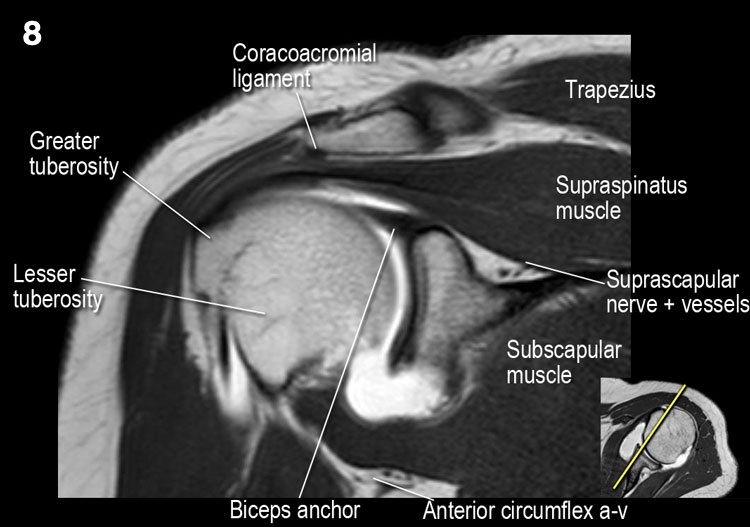

Giải phẫu mặt cắt vành và danh sách kiểm tra

- Lưu ý dây chằng quạ-đòn và đầu ngắn cơ nhị đầu.

- Lưu ý dây chằng quạ-mỏm cùng vai.

- Lưu ý thần kinh và mạch máu trên vai.

- Tìm kiếm hội chứng chèn ép cơ trên gai do gai xương khớp cùng-đòn hoặc dây chằng quạ-mỏm cùng vai dày lên.

- Đánh giá phức hợp sụn viền-gân cơ nhị đầu phần trên và tìm kiếm túi cùng dưới sụn viền hoặc rách SLAP.

- Tìm kiếm tràn dịch quá mức trong túi hoạt dịch dưới mỏm cùng vai và rách gân cơ trên gai.

- Tìm kiếm rách kiểu “rim-rent” của gân cơ trên gai tại chỗ bám của các thớ sợi trước.

- Đánh giá chỗ bám của dây chằng ổ chảo-cánh tay dưới (IGHL) vào xương cánh tay. Đánh giá phức hợp sụn viền-dây chằng phần dưới. Tìm kiếm tổn thương HAGL (bong điểm bám dây chằng ổ chảo-cánh tay tại xương cánh tay).

- Tìm kiếm rách gân cơ dưới gai.

- Lưu ý tổn thương Hill-Sachs nhỏ.

- Đánh giá điểm neo gân cơ nhị đầu.